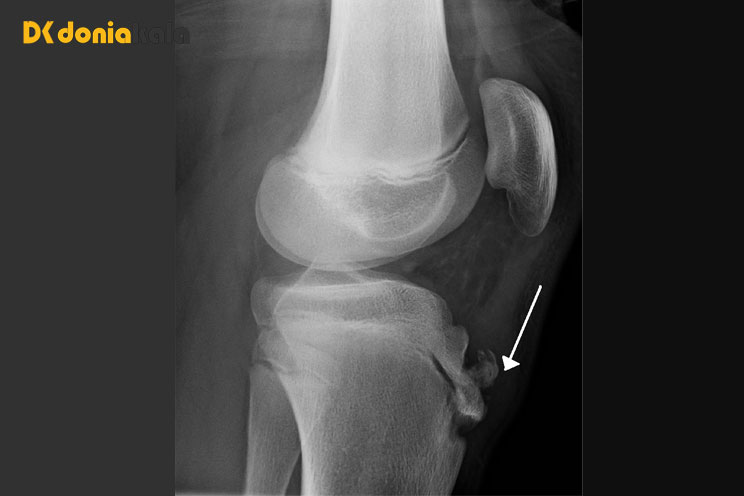

اشعه ایکس از زانو، شناسایی محل صفحات رشد:

تاندون کاسه زانو (کشکک) به صفحه رشد در جلوی استخوان ساق پا (درشت نی) متصل می شود. ماهیچه های ران (چهارسر ران) به کشکک می چسبند و وقتی کشکک را می کشند، کشکک را تحت فشار قرار می دهد. سپس تاندون کشکک استخوان درشت نی را در ناحیه صفحه رشد می کشد. هر حرکتی که باعث کشیدگی مکرر ساق شود میتواند منجر به حساسیت در نقطهای که تاندون کشکک به بالای استخوان درشت نی میچسبد، شود. فعالیتهایی که به زانو فشار وارد میکنند - بهویژه چمباتمه زدن، خم شدن یا دویدن در سربالایی (یا پلههای ورزشگاه) - باعث میشوند بافت اطراف صفحه رشد آسیب ببیند و متورم شود. همچنین ضربه زدن به ناحیه حساس دردناک است. زانو زدن می تواند بسیار دردناک باشد.